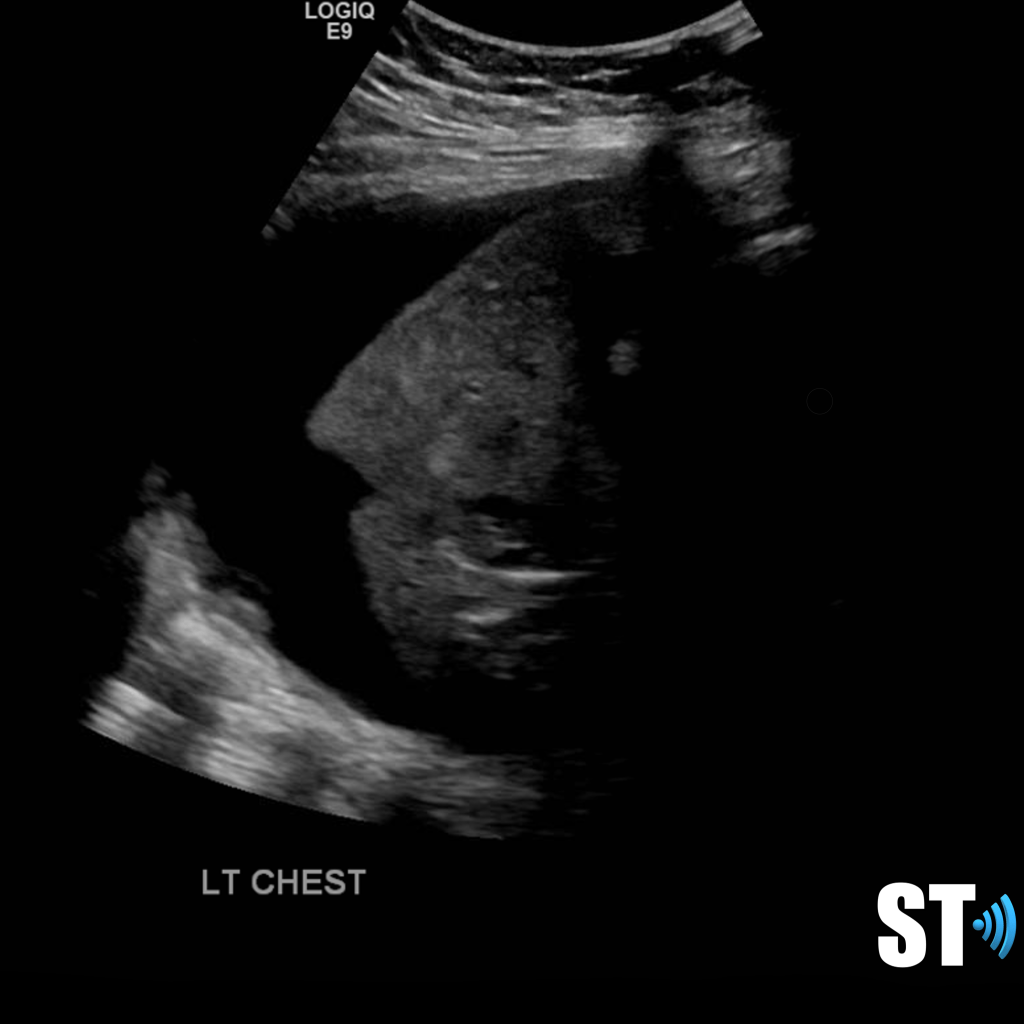

Large volume pleural effusion

Large volume echogenic pleural effusion

Large and or symptomatic pleural effusions may be treated with ultrasound guided thoracentesis which can double as a diagnostic procedure, where the fluid removed can be sent to pathology. Normal analysis of the fluid consists of cytology, chemistry and culture.